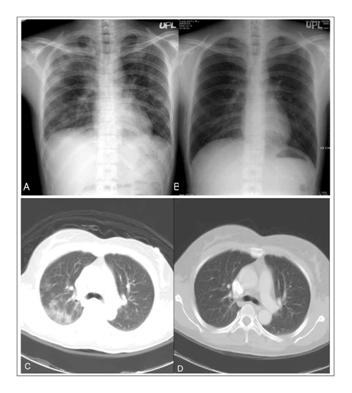

Ngoài ra, các phát hiện khác khi xét nghiệm có thể bao gồm thiếu máu nhẹ, giảm tiểu cầu nhẹ, tăng aminotransferase và tăng bilirubin trong huyết thanh [7]. Nước tiểu và nước bọt người mắc bệnh sốt rét bằng kỹ thuật sinh học phân tử phát hiện P. falciparum [11]. Một số trường hợp sốt rét do P. falciparum nặng [11], chụp x quang phổi thấy hình ảnh thâm nhiễm kẽ hai bên (bilateral interstitial infiltrates), phù phổi, tràn dịch màng phổi [11]. Sanklecha và cộng sự đã báo cáo ba trường hợp là thiếu niên nhiễm sốt rét P. falciparum trong một gia đình và phát hiện ra hai trường hợp đã được chứng minh có tổn thương phổi hai bên, trong khi trường hợp còn lại thấy bình thường khi chụp x quang phổi thẳng [12]. Ảnh chụp x quang ở ba trường hợp mắc bệnh sốt rét bị thiếu máu hồng cầu hình liềm cũng được báo cáo tất cả các bệnh nhân đã chứng minh thâm nhiễm phổi hai bên [13]. Ảnh chụp x quang phổi thường không đặc hiệu, nhưng họ cần phải được ghi nhận trong vùng lưu hành sốt rét nặng [13]. Ảnh chụp x quang phổi ở bệnh nhân sốt rét P. vivax chứng minh thâm nhiễm phổi hai bên, trong đó chỉ ra hội chứng suy hô hấp cấp tính [14]. Ba trường hợp suy hô hấp dạng suy hô hấp cấp tính ở người lớn (Adult Respiratory Distress Syndrome_ARDS) do nhiễm P. vivax cũng đã được báo cáo ở Ấn Độ, trong đó một ca đã được chứng minh với biểu hiện thâm nhiễm quanh rốn phổi hai bên, một ca với độ mờ đục lan rộng hai bên và một ca còn lại độ mờ sáng từ đáy phổi lên đến hai bên trên hình ảnh chụp x quang phổi [15].